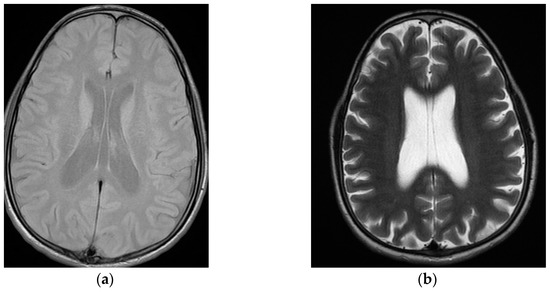

Schizophrenia Misdiagnosis after Capgras and Cotard Delusions in a Patient with Infantile Cystinosis, Cavum Septi Pellucidi, Cavum Vergae and Cavum Veli Interpositi

2. Case Presentation